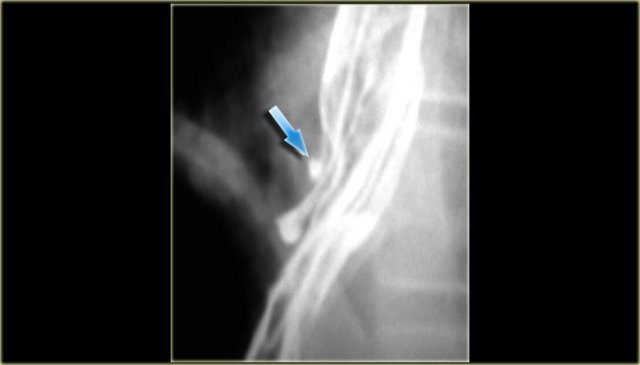

On the left a high stricture (arrow) following caustic ingestion